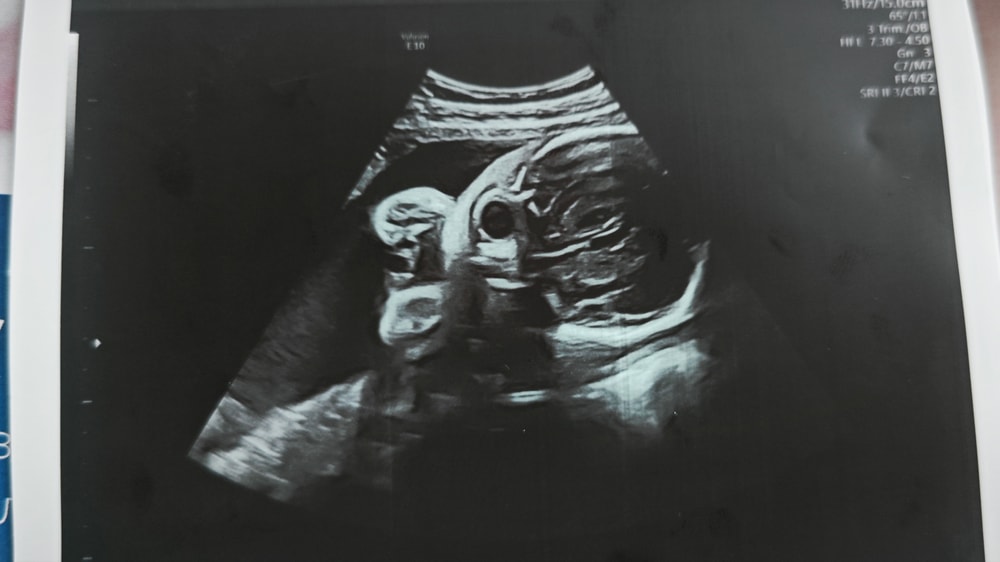

Фото с УЗИ 28 недель

Сходила в частную клинику на УЗИ в 28 недель, сказали, что всё хорошо ттт, и дали фото. И вот когда я уже вышла с клиники и увидела фото, я вообще ничего не поняла. Это вроде голова, но вообще непонятно что где и выглядит жутковато...

Может тут кто-то разбирается или понимает что где на этих фото?

Анастасия , ну а что вы хотели от 2d узи? У вас все ок, видны глазницы. Лобные доли, нос. Сходите на цветное 3d, там черты лица увидите.